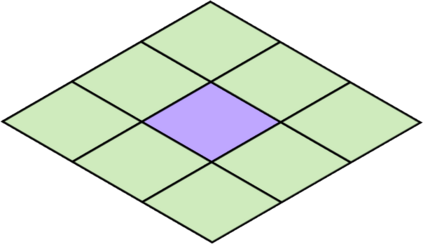

Deep Convolutional Neural Networks (DCNNs) are used extensively in biomedical image segmentation. However, current DCNNs usually use down sampling layers for increasing the receptive field and gaining abstract semantic information. These down sampling layers decrease the spatial dimension of feature maps, which can be detrimental to semantic image segmentation. Atrous convolution is an alternative for the down sampling layer. It increases the receptive field whilst maintains the spatial dimension of feature maps. In this paper, a method for effective atrous rate setting is proposed to achieve the largest and fully-covered receptive field with a minimum number of atrous convolutional layers. Furthermore, different atrous blocks, shortcut connections and normalization methods are explored to select the optimal network structure setting. These lead to a new and full-scale DCNN - Atrous Convolutional Neural Network (ACNN), which incorporates cascaded atrous II-blocks, residual learning and Fine Group Normalization (FGN). Application results of the proposed ACNN to Magnetic Resonance Imaging (MRI) and Computed Tomography (CT) image segmentation demonstrate that the proposed ACNN can achieve comparable segmentation Dice Similarity Coefficients (DSCs) to U-Net, optimized U-Net and hybrid network, but with significantly reduced trainable parameters due to the use of full-scale feature maps and therefore computationally is much more efficient for both the training and inference.